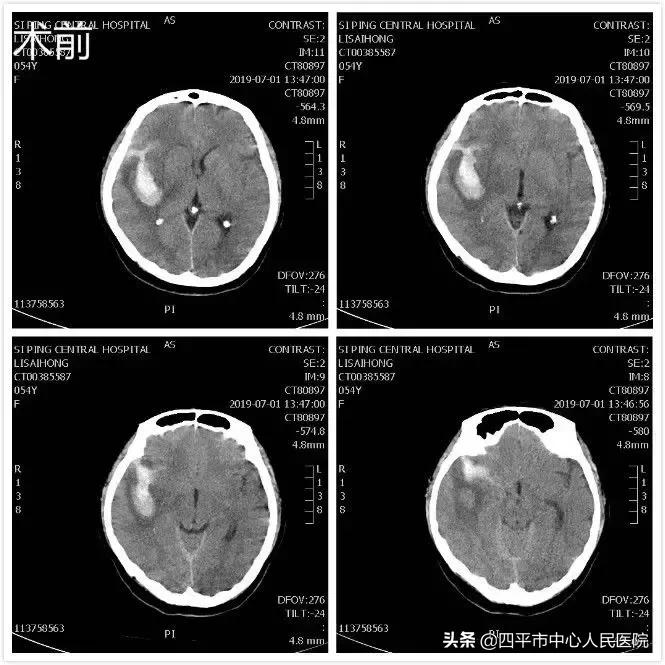

Case3 前交通动脉瘤和左侧脉络膜前动脉动脉瘤

患者李XX,于入院前3小时无明显诱因突发剧烈头痛,以双侧颞部为著,恶心、呕吐数次,呕吐物为胃内容物,发病后急被家属送至双辽市中心医院,急行头部CT发现蛛网膜下腔出血,经治疗头痛未见缓解,考虑动脉瘤破裂出血,夜间转到我院后行头部CTA检查示前交通动脉瘤及左侧脉络膜前动脉动脉瘤。李晓东主任带领王野凌晨急诊全麻下经左侧翼点入路行前交通动脉瘤及脉络膜前动脉动脉瘤夹闭术,先夹闭责任病灶--前交通动脉瘤,保护穿支血管,然后,仔细解剖夹闭脉络膜前动脉动脉瘤,保护脉络膜动脉避免误夹,术后患者恢复良好,神清语明,四肢活动自如。该例颅内多发动脉瘤患者病情重,难度系数较高,术后未遗留任何神经功能障碍,家属送锦旗表达谢意。